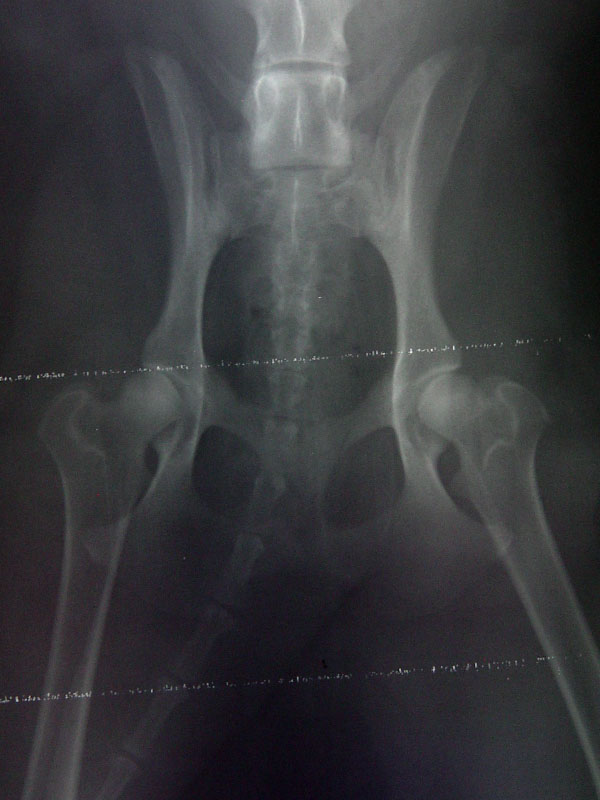

this is an x-ray of our dog laying on his back.

if you look at the 2 femurs, you can see the ball/socket on his right femur (left side of the photo) has a nice narrow area after the "ball" this allows the bone to freely move around in the socket.

the left femur is the problem - there is no narrow part after the ball. the bone is just right there on the ball, which doesn't allow the leg to move as freely in his hip socket. it just sort of rocks around in there.